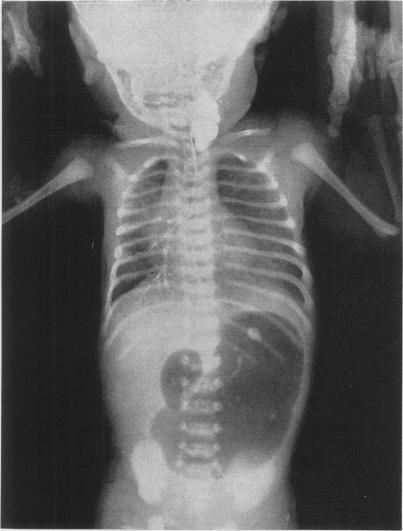

Congenital atresia of the esophagus with tracheo-esophageal fistula; treatment of surgical complications.

Ann Surg. 1955 Aug;142(2):204-13. doi: 10.1097/00000658-195508000-00006.